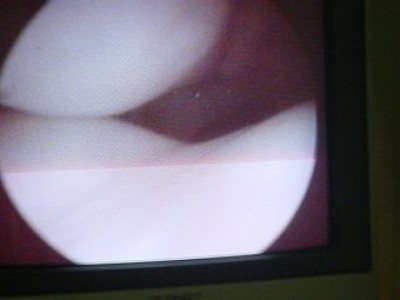

Luxación Habitual de Rótula

Envíado por Dr. Eduardo E. Martínez Melara